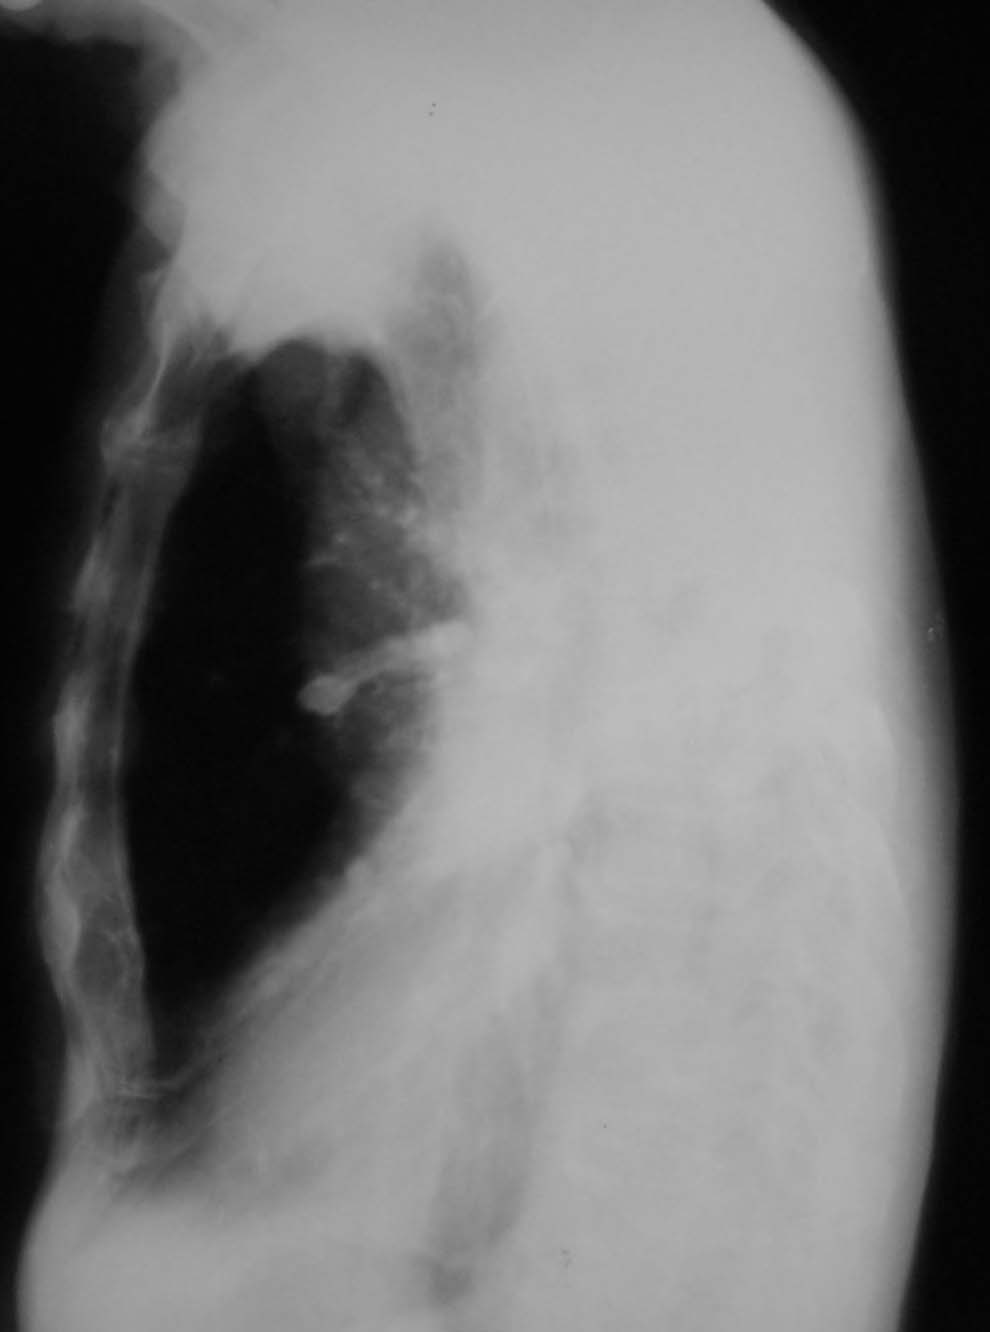

以下是引用jian-5587在2006-11-3 19:10:00的发言:[br]左侧胸廓塌陷,纵隔向左侧移位,左肺密度增高,但在上野见多发小斑片状气体密度影,左侧膈肌消失,考虑左肺占位所致肺不张可能性大,不排除左肺结核所致可能,建议进一步检查.右上肺陈旧结核病灶.

以下是引用jiangjing在2006-11-3 20:25:00的发言:[br]左侧胸廓塌陷,纵隔向左侧移位,左肺密度增高,但在上肺野可见部分含气肺组织影,左侧膈面消失,右上肺见多发班点状钙化灶,右肺代偿性肺气肿,右肺部分经纵隔疝入左侧胸腔,左侧胸膜增厚。考虑,肺结核致左肺毁损[肺硬化],右侧钙化灶,左侧胸膜增厚,右肺肺气肿。建议ct检查排除左肺新生物所致肺不张。

以下是引用dyqct在2006-11-3 21:48:00的发言:[br]支持:1、左肺结核致左肺毁损[肺硬化];[br] 2、右上肺陈旧性肺结核;[br] 3、建议ct进一步检查。